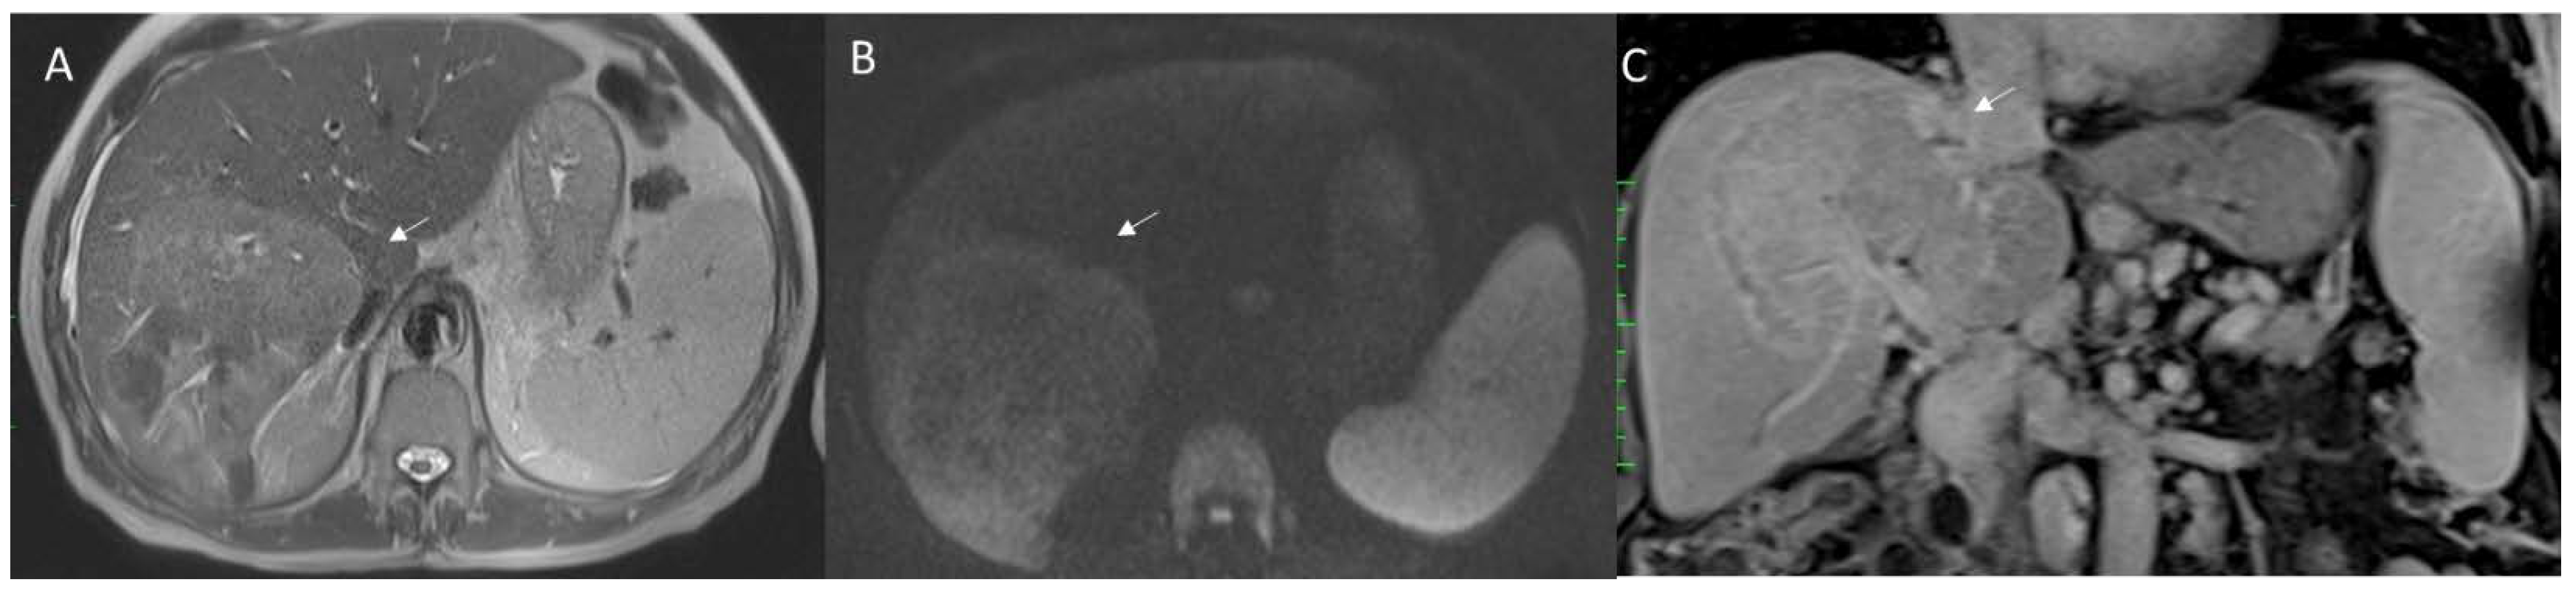

Figure 2. HCC EOB-MRI assessment. The lesion shows (arrow) hyperinthense signal on T2-W: (A) sequences, (B) arterial hyperenanchement during arterial phase of contrast study, (C) wash-out appearance during portal phase, and (D) hypointense signal during hepatospecific phase.

With regard to contrast agents in MRI liver studies, today, two types of agents could be used. According to the different phase of patient management, the study protocols can include the possibility to administrate a liver-specific contrast (in pre-surgical settings) and a non-liver-specific contrast (in the characterization and staging phases). Liver-specific contrast agents can also be used to assess functional liver failure in both patients with hepatocellular carcinomas (HCC) (Figure 2) and in liver metastatic patients (Figure 3). Therefore, to understand the pattern of the lesion during the study of the contrast medium and the functionality of the liver parenchyma, the radiologist should clarify the type of agent used. Furthermore, the contrast agent is a drug and could cause a reaction, so these data should be reported in a SR.